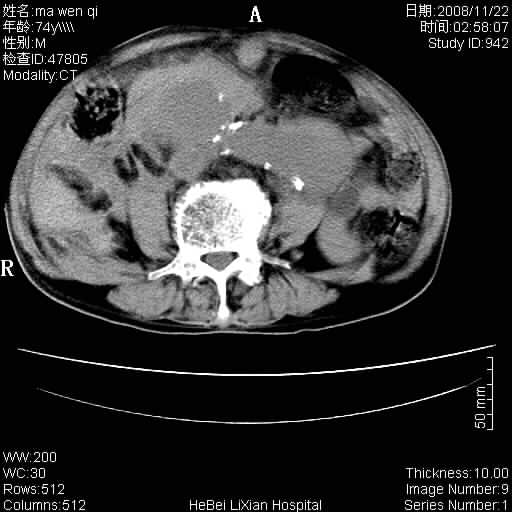

患者男 74岁.突然昏迷,休克6小时.血压70/30,头颅ct未见异常,既往体健.

补充病史,保留导尿10小时,尿袋内只有少许尿液,患者于住院后15小时后去世.

腹主动脉、双侧髂动脉夹层动脉瘤破裂出血进入腹腔。

1)考虑双侧髂动脉瘤并右侧动脉瘤破裂出血,右侧腹膜后及腹腔积血。2)双侧腹股沟疝。

1)考虑,腹主动脉、双侧髂动脉夹层动脉瘤破裂伴右侧腹膜后及腹腔积血。2)双侧腹股沟疝。